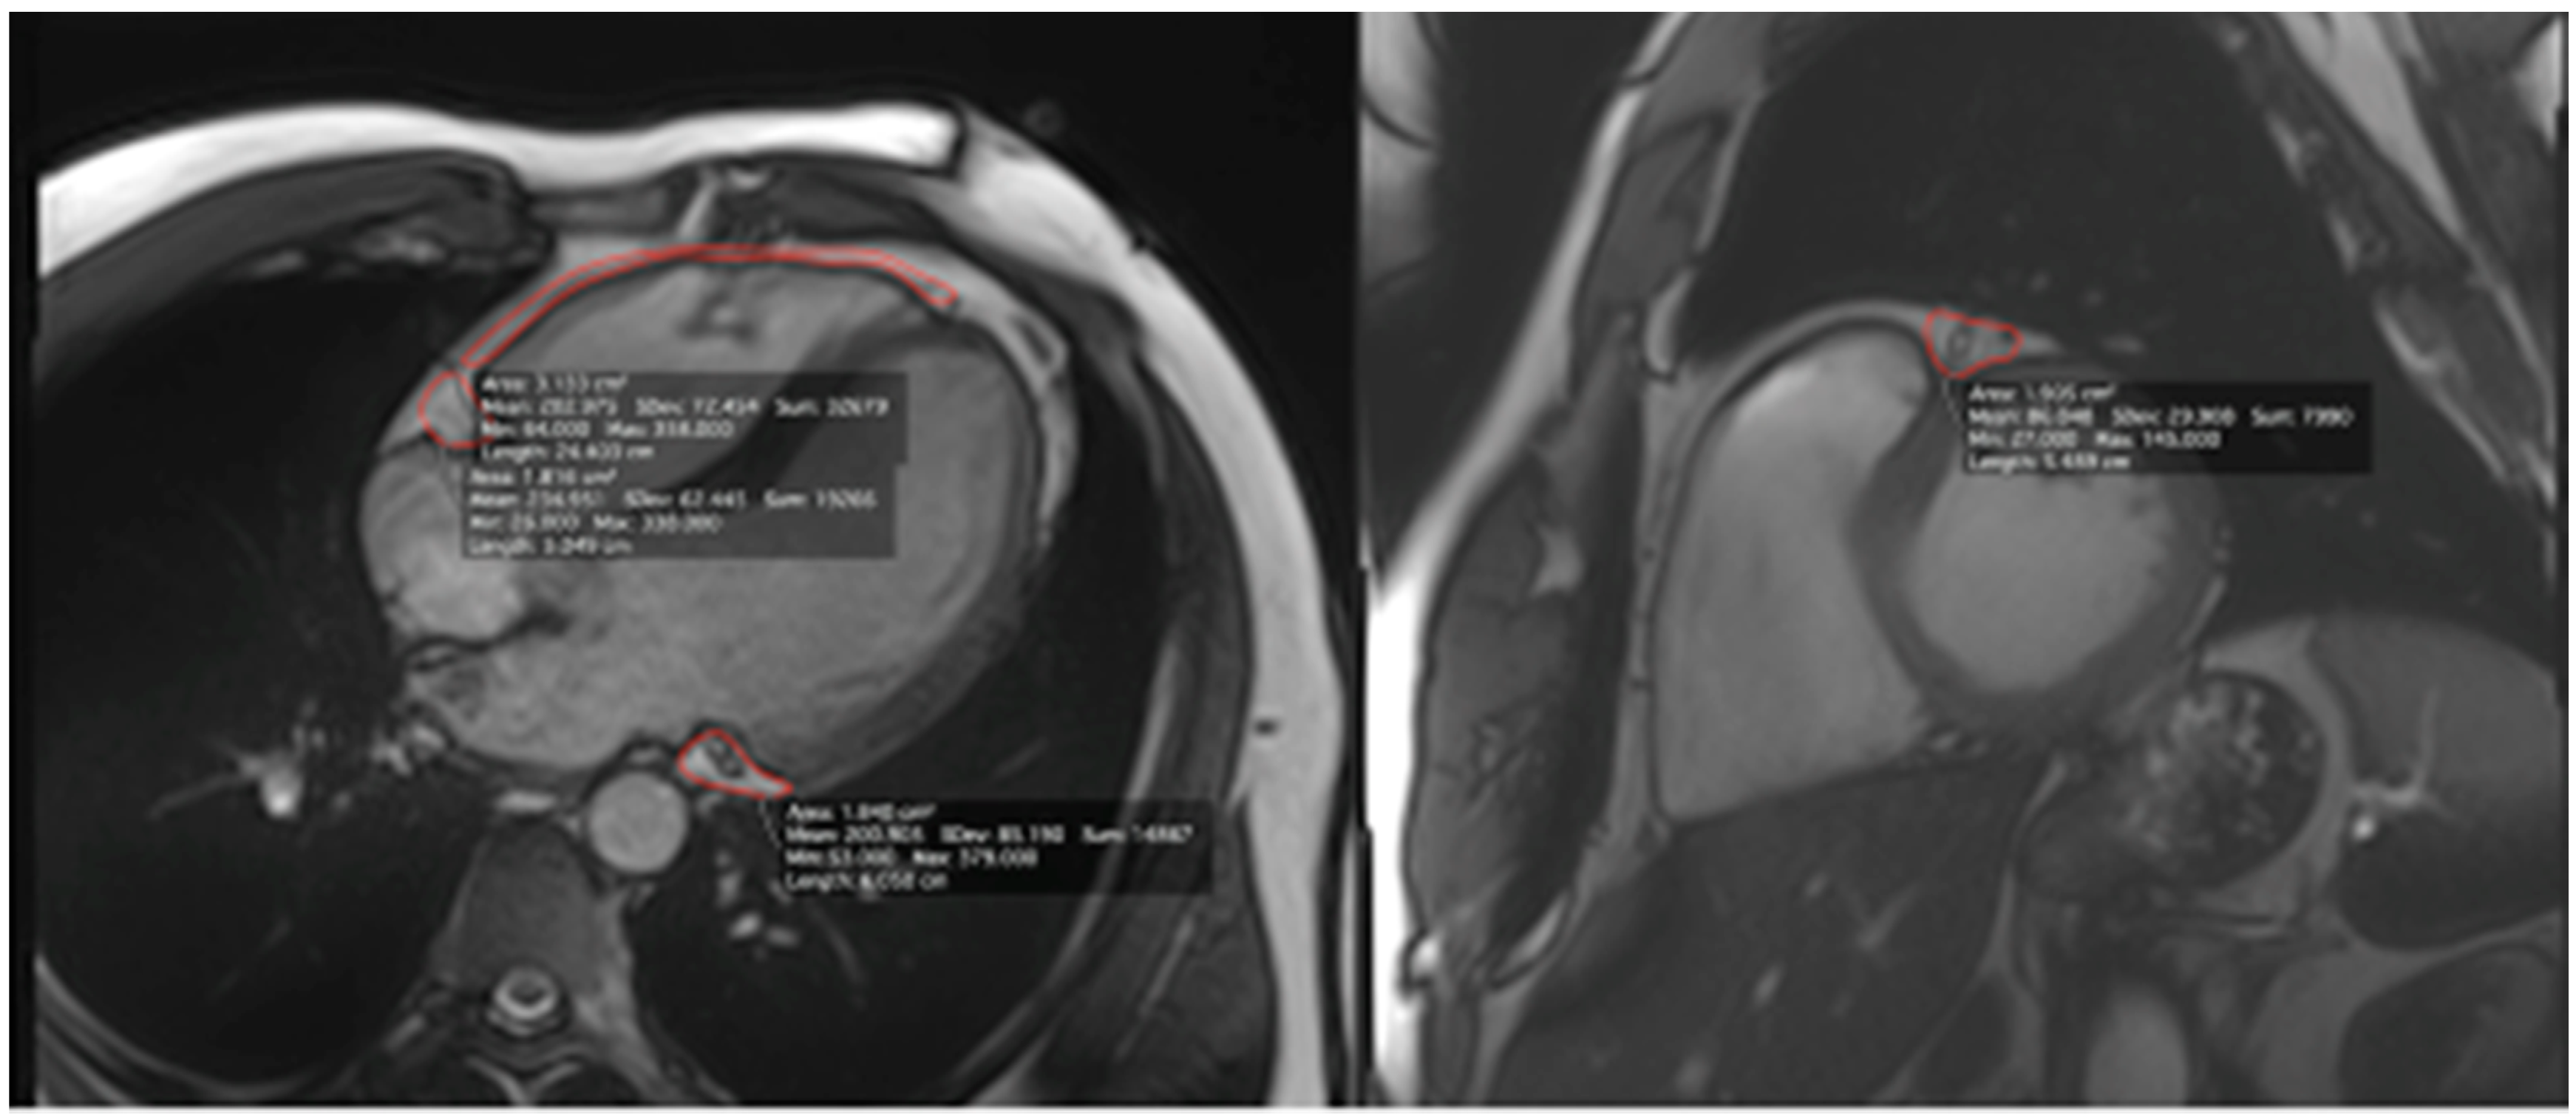

| Cardiac Magnetic Resonance | |||

| Parameter | Ultra-marathon Runners (n = 30) | Control Group (n = 9) | p |

| LAD (cm2) | 1.12 ± 0.4 | 1.86 ± 0.41 | <0.001 |

| RCA (cm2) | 0.88 ± 0.39 | 1.78 ± 0.34 | <0.001 |

| Cx (cm2) | 0.90 ± 0.36 | 1.74 ± 0.49 | <0.001 |

| RV (cm2) | 2.07 ± 0.97 | 5.23 ± 2.77 | <0.001 |